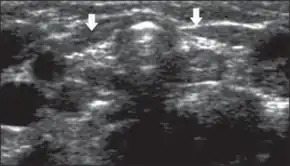

If the TSH is high, or the T4 low, the infant's doctor and parents are called and a referral to a pediatric endocrinologist is recommended to confirm the diagnosis and initiate treatment. A technetium (Tc-99m pertechnetate) thyroid scan detects a structurally abnormal gland, while a radioactive iodine (RAIU) exam identifies congenital absence or a defect in organification (a process necessary to make thyroid hormone).